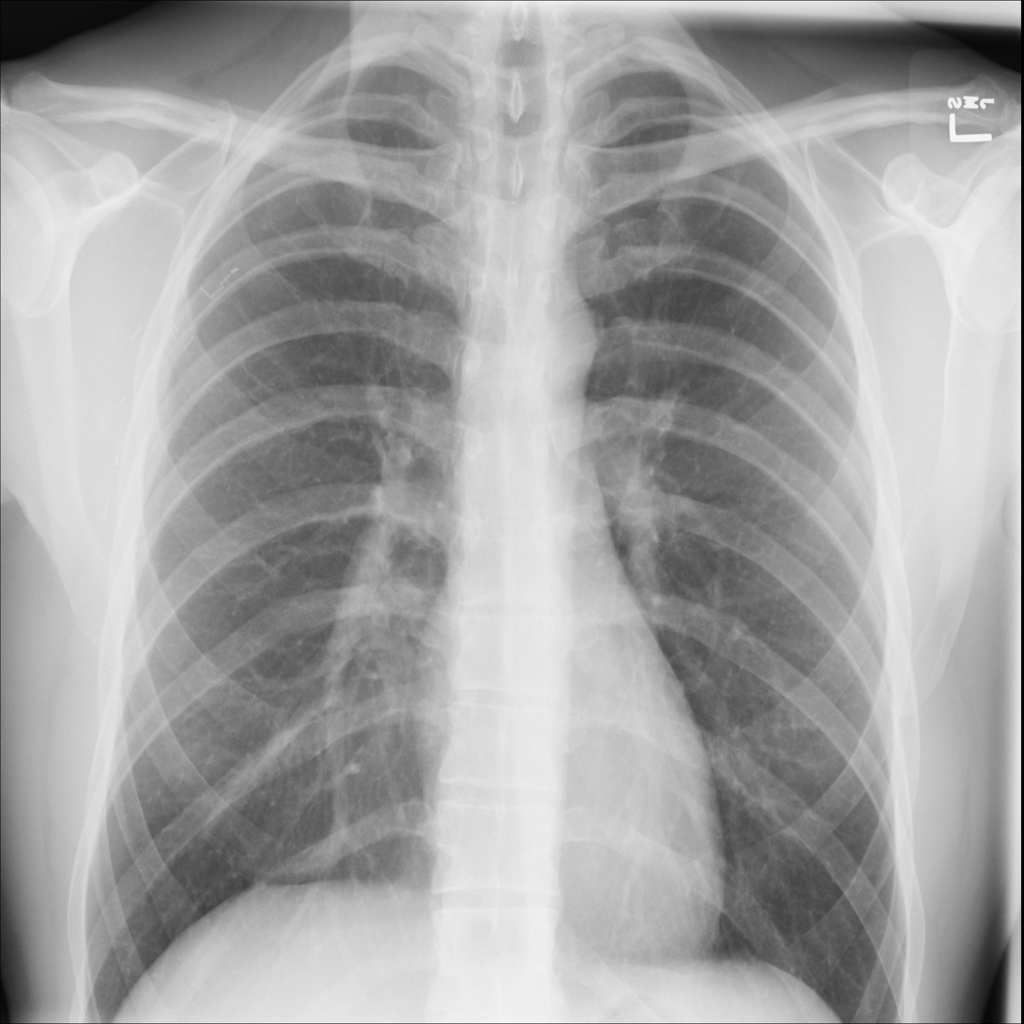

PAT-304B · IMG-000Hernia

PAT-304B · IMG-000

PA